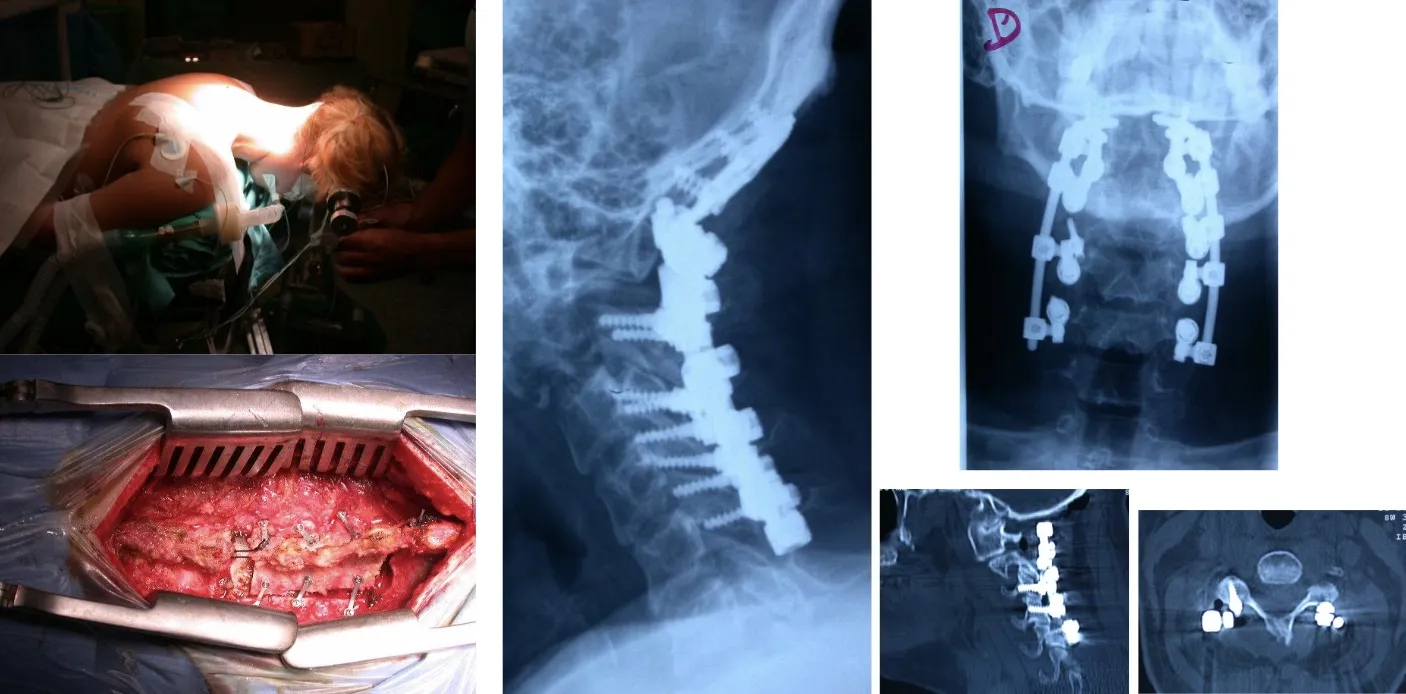

Otra opción es acceder por vía posterior, lo que permite realizar una fijación más sólida y estable mediante la colocación de tornillos y barras en los elementos posteriores de la columna. Este tipo de abordaje ofrece un mayor refuerzo estructural, especialmente útil cuando existe pérdida de sostén anterior o es necesario complementar una reconstrucción realizada previamente por vía anterior.

También es posible realizar el abordaje por vía posterior, a través del cual se pueden efectuar tanto la resección de los tumores como la colocación de los sistemas de fijación necesarios para estabilizar la columna, tal como se observa en la figura. Este abordaje permite al cirujano acceder directamente a las estructuras posteriores vertebrales y realizar una descompresión neurológica precisa cuando existe afectación del canal raquídeo.

Hoy en día disponemos de la capacidad técnica y humana, gracias a la colaboración con otros especialistas, para llevar a cabo grandes intervenciones quirúrgicas en la columna lumbar, procedimientos que hace apenas unos años presentaban una morbilidad tan elevada que los hacía desaconsejables tanto para los cirujanos como para los propios pacientes.

Este es un ejemplo de las intervenciones de gran envergadura que en ocasiones es necesario realizar, como en el caso de las cirugías de la región sacra, donde la complejidad anatómica y la proximidad de estructuras vitales exigen una planificación meticulosa y un abordaje multidisciplinario.